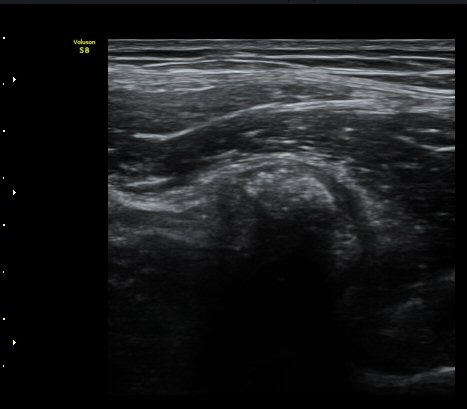

¼±»óŽÃÊÀÚ¸¦ ÀÌ¿ëÇÑ °Ë»ç¿¡¼­ ÀüÇÏÀ屨ÀÇ ´ëÅðÁ÷±Ù ±â½ÃºÎ¿¡ ¼®È¸È­ À½¿µÀÌ ¶Ñ·ÈÈ÷

°üÂûµÊ(»çÁø 4, 5).